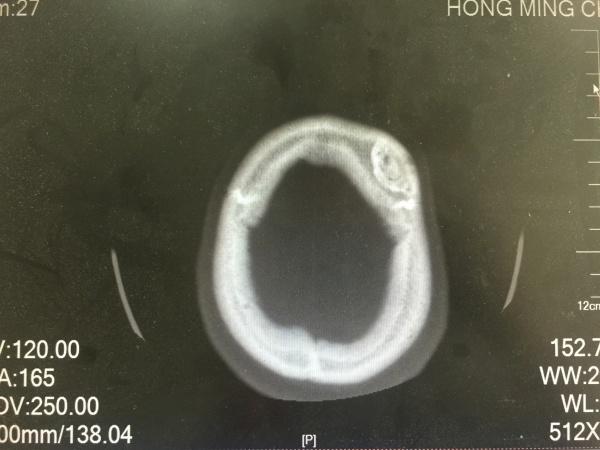

昨夜一位醉酒后外伤的病人,予以头颅CT检查发现的颅骨骨瘤,看着像在板障内,因患者醒酒后家属已送其回家,询问平素无明显不适,故无法跟踪及进一步明确。

请爱友们发言,考虑何种性质?